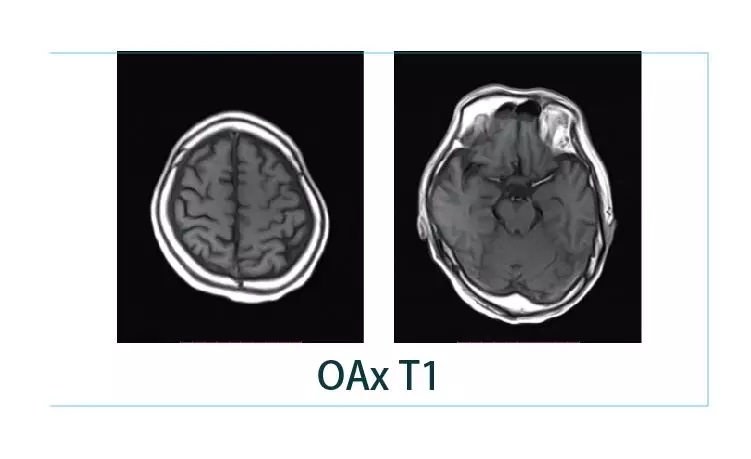

【朗润影像档案】20190216磁共振影像病例结果讨论

【朗润影像档案】20190125磁共振影像病例结果讨论

【朗润影像档案】20190118磁共振影像病例结果讨论

【朗润影像档案】20190111磁共振影像病例结果讨论

【朗润影像档案】20190104磁共振影像病例结果讨论

【朗润影像档案】20181229磁共振影像病例结果讨论

【朗润影像档案】20181221磁共振影像病例结果讨论

【朗润影像档案】20181214磁共振影像病例结果讨论

【朗润影像档案】20181207磁共振影像病例结果讨论

【朗润影像档案】20181130磁共振影像病例结果讨论

【朗润影像档案】20181123磁共振影像病例结果讨论

【朗润影像档案】20181116磁共振影像病例结果讨论